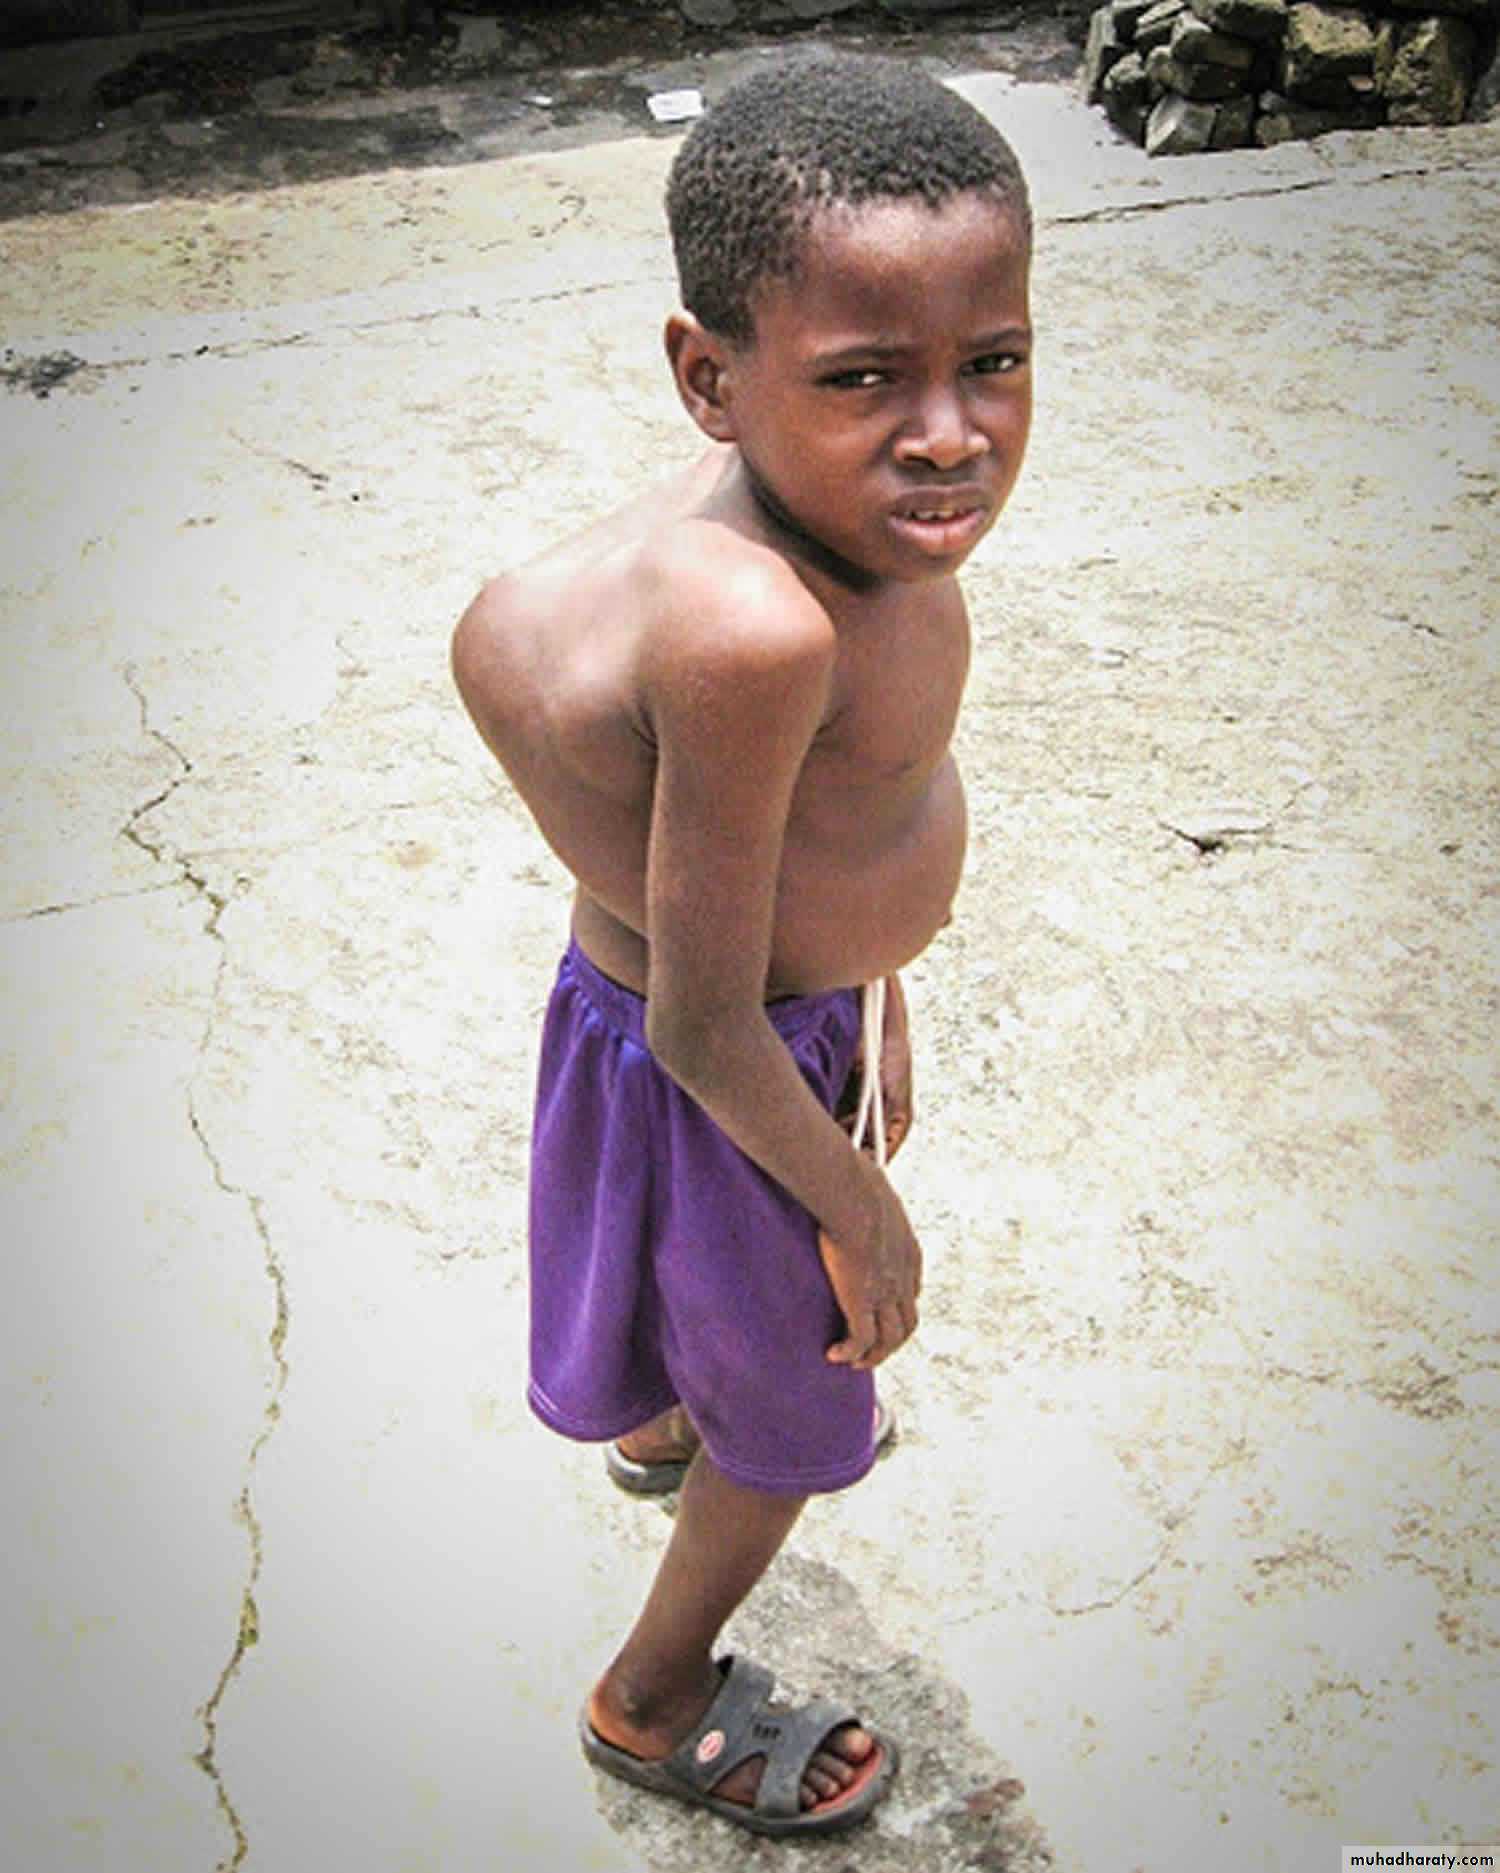

In the spine, pain may be slight. Consequently the patient may not present until there is a visible abscess (usually in the groin or the lumbar region to one side of the midline) or until collapse causes a localized angular kyphosis (gibbus).